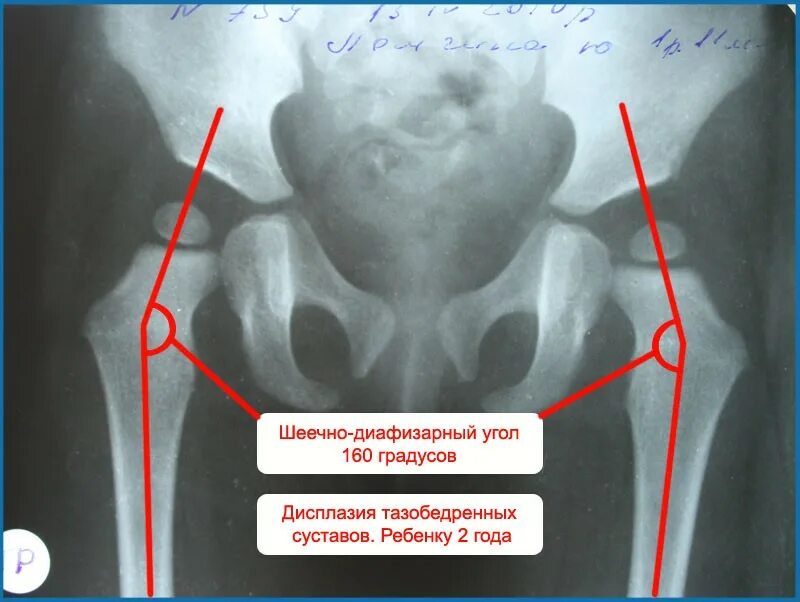

Мкб дисплазия тазобедренных суставов детей